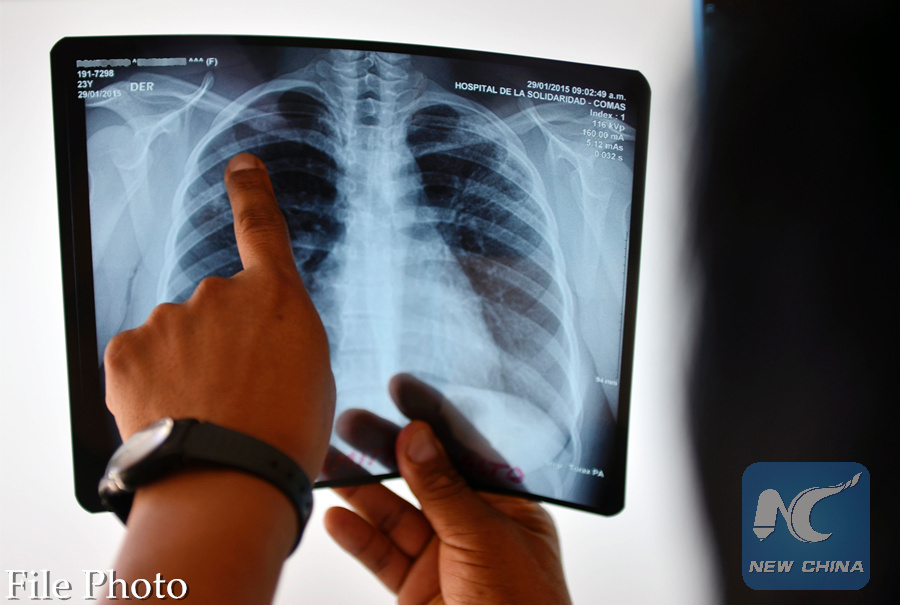

This file photo taken on April 14, 2015 shows a medical doctor checking an x-ray film at a public clinic of a poor district in Lima. (AFP Photo)